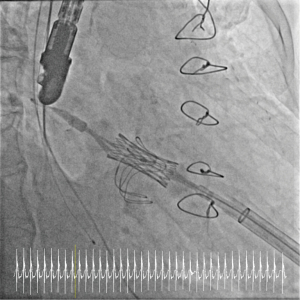

All procedures were performed under general anesthesia in the presence of our institutional Heart Team in a specially equipped hybrid operating room, offering full functionality for cardiac catheterization, anaesthesiology, and cardiac surgery, and a cardiopulmonary bypass circuit and clinical perfusion team were kept on stand-by. The transapical access was performed as previously described by our group (7) using four pledged U-stitches (Prolene 3-0, MH needle). In brief, access to the left ventricular apex was obtained by a 4–6 cm anterolateral minithoracotomy in the fourth, fifth or sixth intercostal space. After puncturing the apex, a soft guidewire was advanced under fluoroscopic guidance into the right pulmonary vein across the diseased mitral valve. Then, via a Pigtail catheter, an Extra-Stiff wire for further guidance was exchanged for the soft wire, and a transapical sheath (18–26 F sheath depending on valve type) was advanced. The reversely crimped transcatheter valve was finally deployed under ventricular overpacing (120 bpm). The landing zone was identified mainly with fluoroscopic guidance (Figures 1,2). Device function was evaluated by transesophageal echocardiography. Heparin was administered with an intended activated clotting time (ACT) time >250 s.